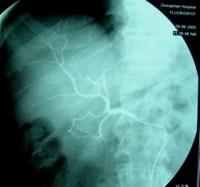

可进行必要的检查化验。若血常规显示小细胞性贫血,血沉增快,大便潜血试验持续阳性;X线表现为钡剂充盈缺损,病变肠壁僵硬,蠕动减弱或消失,结肠袋不规则,肠管狭窄或扩张等,即可确定为已患上第五日综合征。